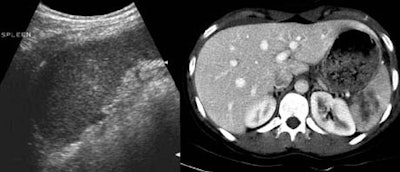

According to the results, CT identified free fluid or organ injury in 112 of 206 patients (54%). The most frequently injured organs were the spleen (39%), liver (30%), kidney (8%), mesenteric bowel (8%), bladder (4%), and the pancreas (3%).

For the depiction of free peritoneal fluid, ultrasound was 92% sensitive at the first pass, and 98% sensitive by the second exam. For overall detection of abdominal injury by either free fluid or organ parenchymal injury, ultrasound was 72% sensitive and 91% specific on the first pass. By the second exam, ultrasound was 91% sensitive and 100% specific.

However, for visceral injury without free fluid, ultrasound was only 41% sensitive and 92% specific on the first pass. By the second exam, sensitivity had risen to 51% and specificity to 100%. A quarter of the organ injuries seen on CT did not have free fluid; therefore the first ultrasound missed 73% of these parenchymal injuries, Poletti said.